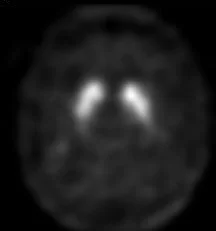

NORMAL DATSCAN

ABNORMAL DATSCAN